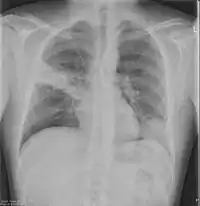

Chest X-rays and X-ray computed tomography (CT) can reveal areas of opacity (seen as white), indicating consolidation.[13] CAP does not always appear on x-rays, sometimes because the disease is in its initial stages or involves a part of the lung not clearly visible on x-ray. In some cases, chest CT can reveal pneumonia not seen on x-rays. However, congestive heart failure or other types of lung damage can mimic CAP on x-ray.[15]

When signs of pneumonia are discovered during evaluation, chest X-rays and examination of the blood and sputum for infectious microorganisms may be done to support a diagnosis of CAP. The diagnostic tools employed will depend on the severity of illness, local practices and concern about complications of the infection. All patients with CAP should have their blood oxygen monitored with pulse oximetry. In some cases, arterial blood gas analysis may be required to determine the amount of oxygen in the blood. A complete blood count (CBC) may reveal extra white blood cells, indicating infection.

X-ray findings indicating hospitalization include:

- Involvement of more than one lobe of the lung

- Presence of a cavity

- Pleural effusion